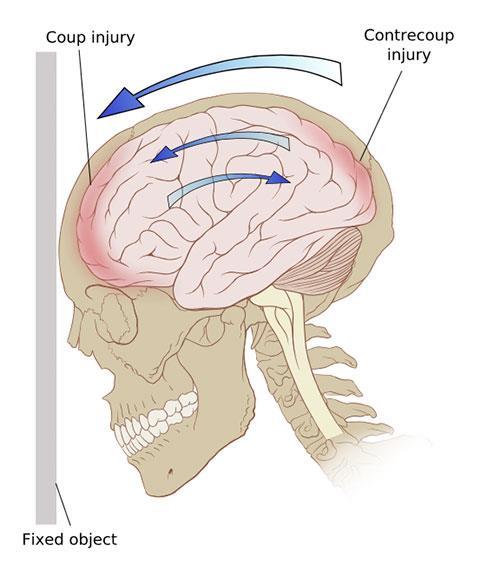

Are a bruising or swelling of the brain that occurs when very small blood vessels bleed into brain tissue. Contusions can occur directly under the impact site (coup injury) or, more often, on the opposite side of the brain from the impact (contrecoup injury). They can appear after a delay of hours to a day. These generally occur when the head abruptly decelerates, which causes the brain to bounce back and forth within the skull (such as in a high-speed car crash or in shaken baby syndrome).